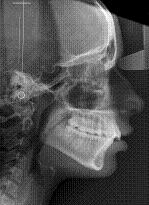

Dependiendo de cada paciente el diagnóstico necesitará una serie de pruebas y estudios complementarios, como pueden ser radiografías, fotos, o modelos de estudio montados en articulador ( este es un dispositivo que simula los movimientos mandibulares).

En algunos pacientes pueden ser necesarias valoraciones concretas dirigidas a diagnosticar alguna patología específica.